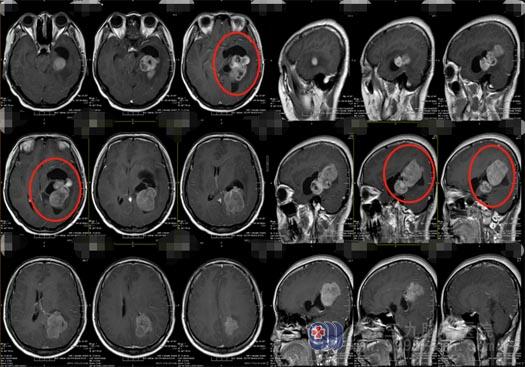

一周前,杨女士在头痛的同时还出现了双侧视物模糊、左侧眼睑也闭合不全;当地医院脑部磁共振检查显示:左侧脑室三角区占位,考虑脑膜瘤。随后家人带着杨女士到多家医院包括北京的天坛医院就诊过,最后选择了在广东三九脑科医院神经外五科进行治疗。

进一步检查发现:杨女士的肿瘤已经压迫导水管,引起了严重的脑积水,病情严重,需要及时进行手术治疗。

医院副院长、神经外五科主任鲁明带领团队对病例进行了详细的讨论:此脑膜瘤血液供应极为丰富,手术治疗出血量大,对术野影响也较大,甚至会因为止血难度大而无法对肿瘤进行完全切除、肿瘤切除后的瘤腔出现不同程度的并发症。最终选择了对患者脑部损伤最小的治疗方案:先行DSA栓塞,由于介入和栓塞治疗的不断发展,手术前根据血管造影结果了解血液供应情况,并进行血管栓塞,可以保证手术治疗的安全性;肿瘤周围主要的血管栓塞后,能大大降低手术中出血的可能,还可以将肿瘤最大范围地切除,更好的保护正常脑组织。

家属也非常赞同该手术方案。12月29日,杨女士先行DSA栓塞,术中可以清晰地看到左侧脑室内异常的染色,呈类圆形,考虑肿瘤占位病变,大小约4cm×4.5cm×4cm,主要由左侧脉络膜后内、左侧脉络膜前动脉末端分支参与供血,将左侧脉络膜后内动脉远端分支血管栓塞,效果明显,肿瘤供血消失,因左侧脉络膜前动脉末端分支血管比较细,微导管到位困难,没有进行栓塞。随后送杨女士至手术室在全麻下行“左侧脑室内占位性病变切除术”。全部手术过程非常的顺利。术后杨女士即清醒,四肢活动无异常。